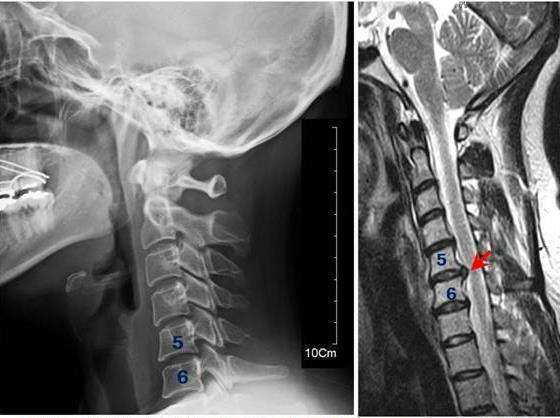

목 주변의 근육, 인대, 디스크 등이 교통사고 과정에서 차량의 후방 추돌 또는 스포츠 손상에 의해 발생되는 가속 및 감속(acceleration & deceleration)에 의한 복합 손상을 편타성 손상(鞭打性損傷,whiplash injury)이라고 합니다. 채찍 손상이라고도 불립니다.

교통사고로 인한 편타성 손상(채찍 손상)이 일어나면 왜 여러 군데가 아픈 걸까요? 편타성 손상은 단순히 목부위의 인대, 근육, 디스크 등에 영향을 미치는 것이 아니라 척추가 가속 및 감속 손상으로 인해 강하게 잡아당겨지고 틀어지면서 손상된 부위 및 아니라 몸 전체에 영향을 미치게 됩니다.

교통사고 후유증의 대표적인 손상인 편타성 손상 또는 채찍 손상(Whiplash injury)은 최근에는 그 손상 기전상 경추 가속/감속 손상(Cervical accelera¬tion/ deceleration injury, CAD)으로 명명되고 있기도 합니다.